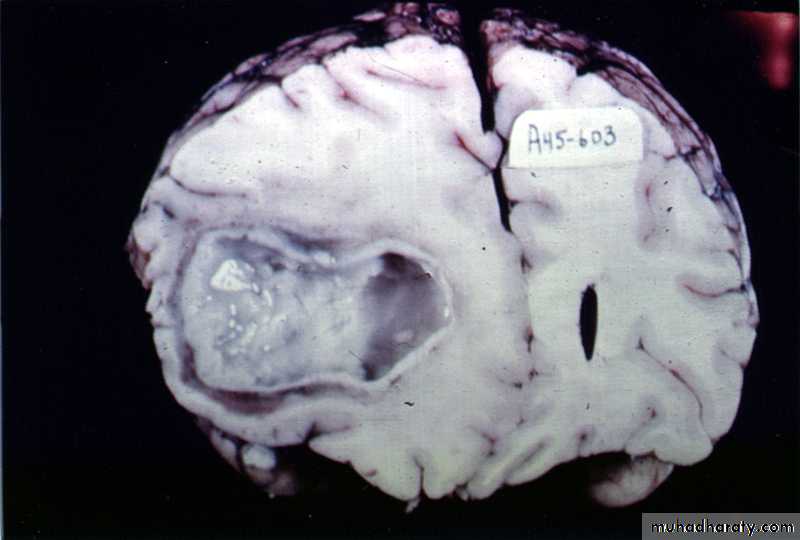

Collagen capsule of brain abscess

Pathology:The formation of a collagen capsule in a developing abscess is the single most important responsible that limits the spread of infection to the rest of the brain.

Brain Abscess Pathology

Brain abscess will pass in four stages:Early cerebritis: early 1-3 days with inflammatory cells.

Late cerebritis: days 4-9, with formation of necrotic core and increasing number of macrophages and fibroblasts.

Early capsule: days 10-13.

Late capsule (mature capsule): by day 14.